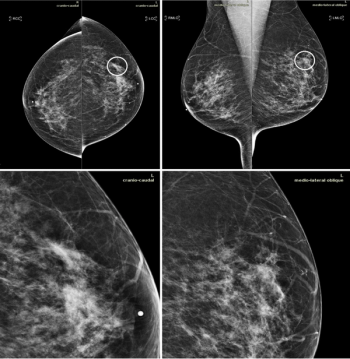

Implementing artificial intelligence tools with breast imaging can pinpoint overlooked interval cancers and decrease provider workload in screening mammography programs.

Not only did this combination improve breast cancer detection, but it could also catch more potentially invasive cancers earlier.

MRI catches more malignant lesions in women with dense breasts who undergo digital breast tomosynthesis than those who have digital mammography alone.